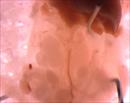

| Mutant 2459-003-2 (E14.5) was harvested with hydrops and abnormal vasculature | b2b2459Clo/b2b2459Clo | C57BL/6J-b2b2459Clo |

| Mutant 2459-003-2 (E14.5) presents with hypoplastic thymus | b2b2459Clo/b2b2459Clo | C57BL/6J-b2b2459Clo |

| Mutant 2459-003-1 (E14.5) is developmentally delayed. Outflow is slightly malrotated which is confirmed to be DORV and ventricular non-compaction by EFIC imaging | b2b2459Clo/b2b2459Clo | C57BL/6J-b2b2459Clo |